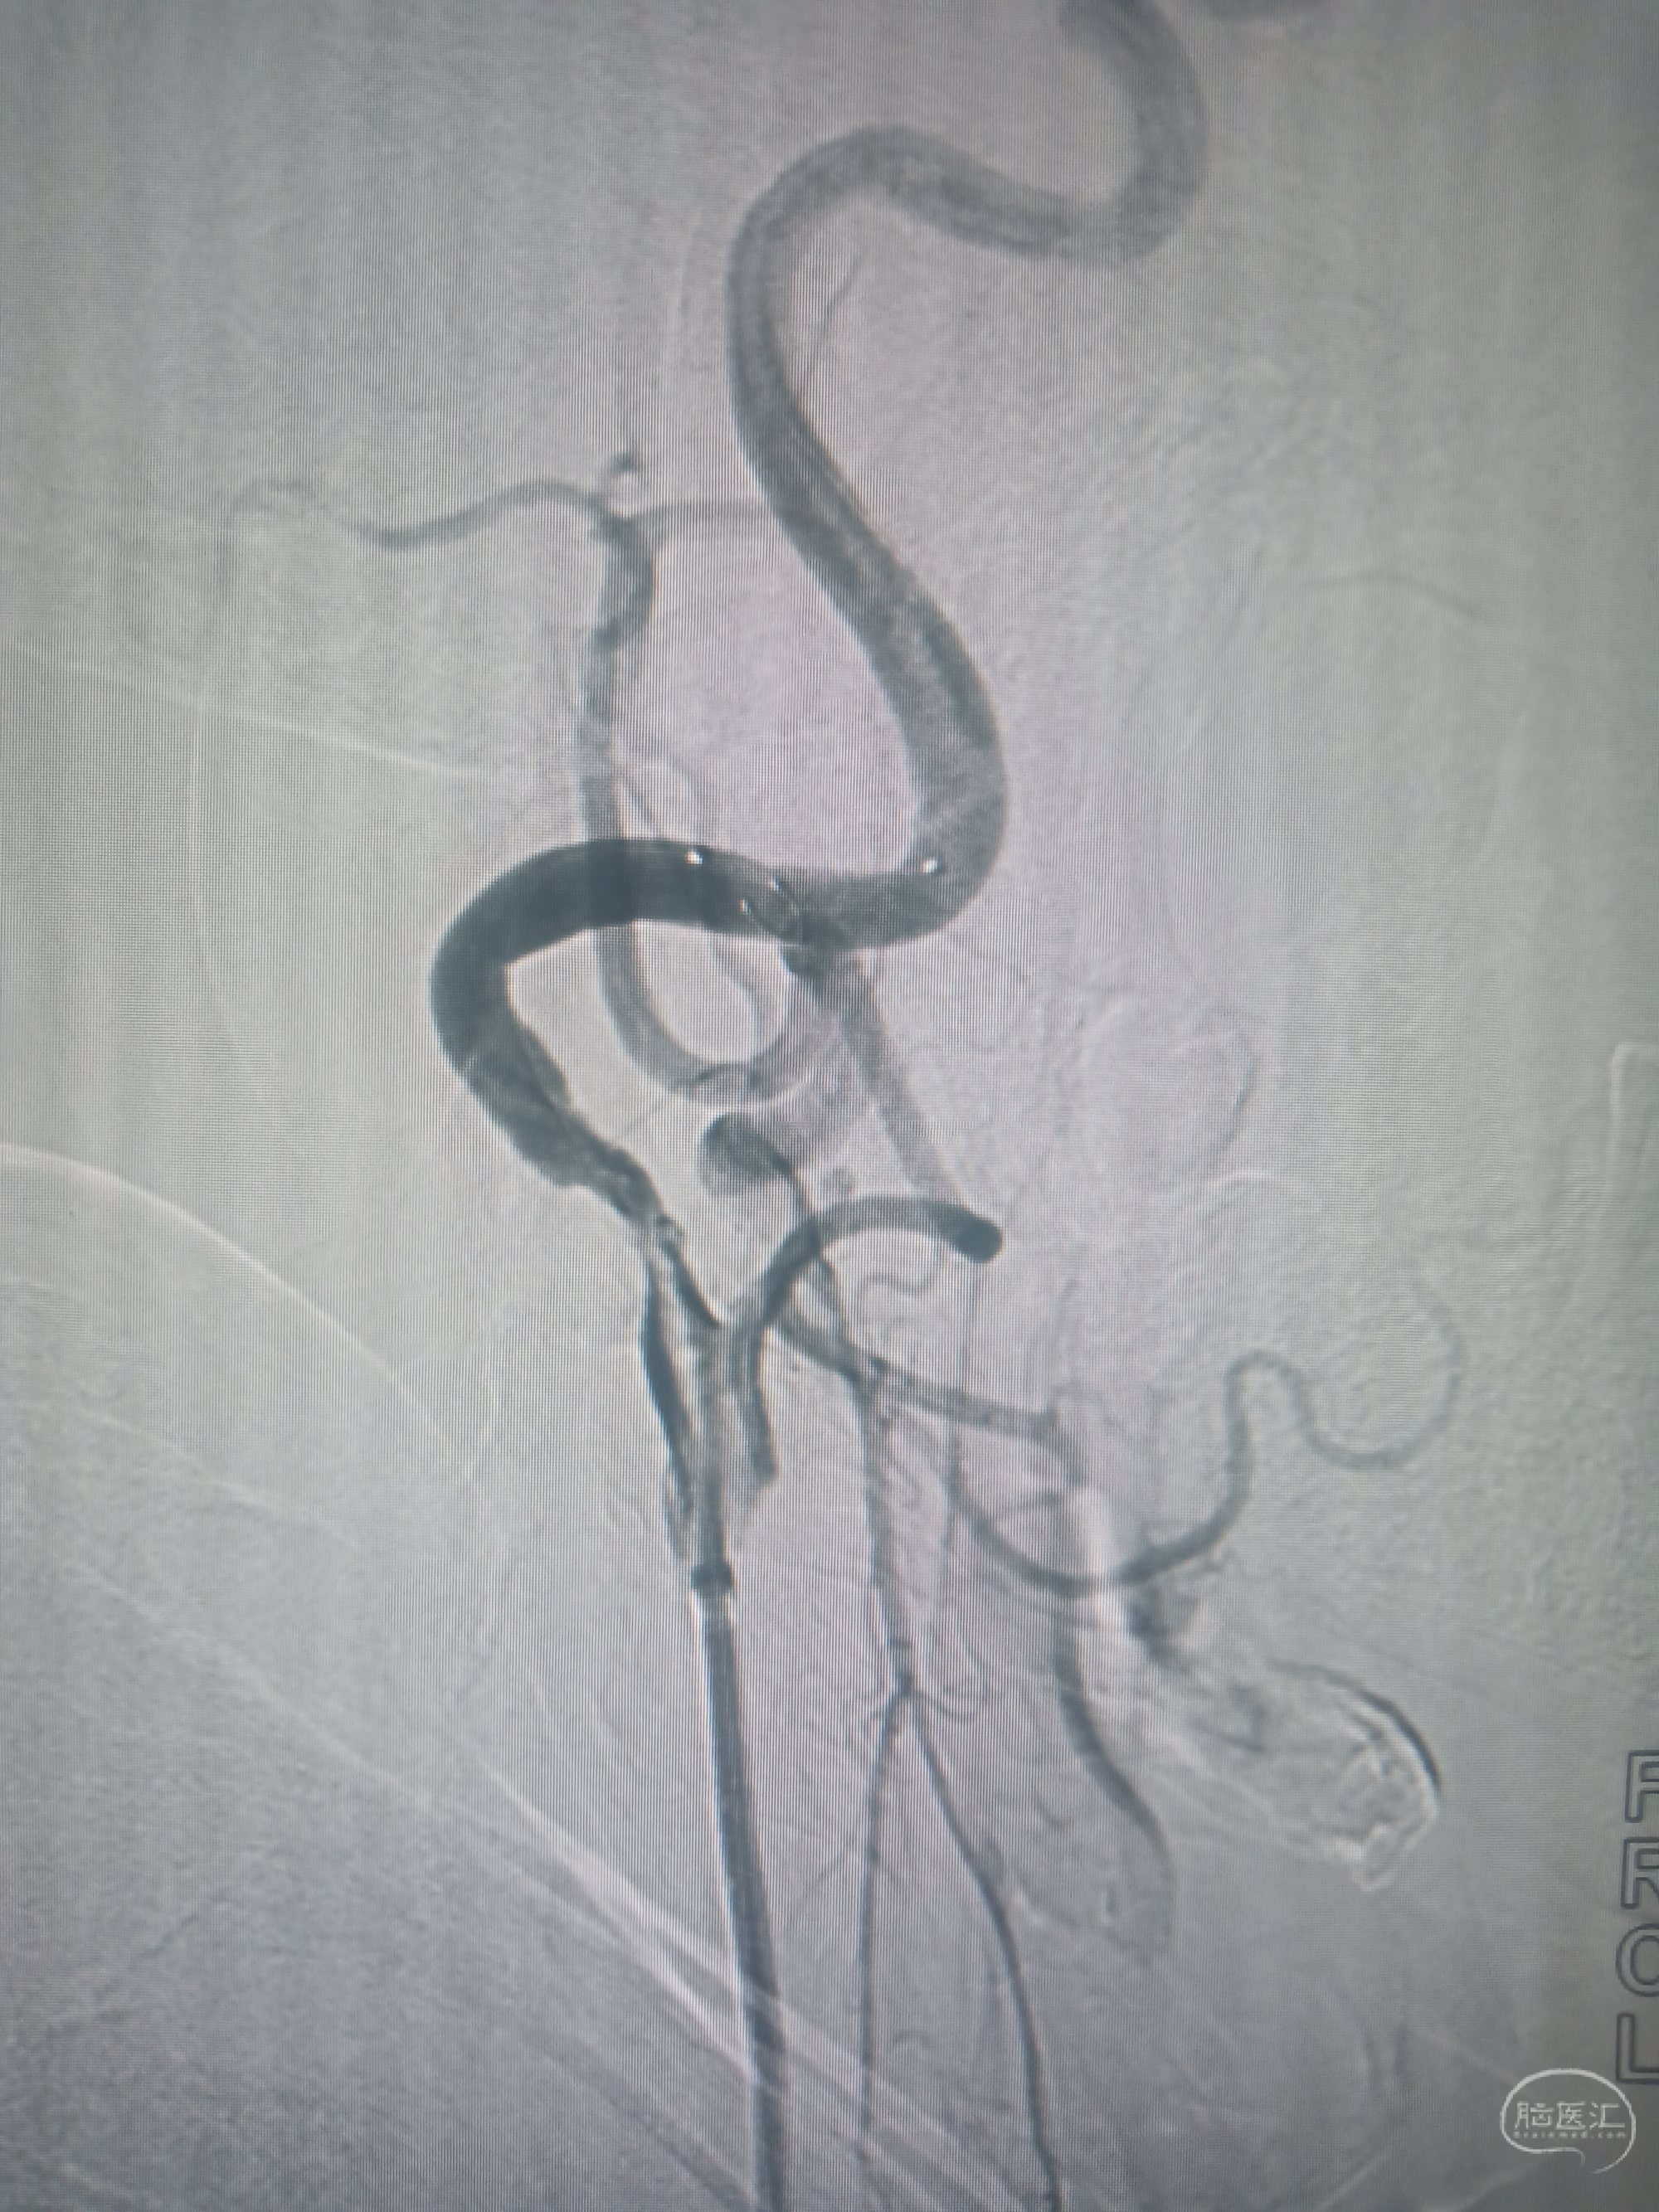

脑血管造影显示:左侧颈内动脉轻度狭窄,右侧颈内动脉起始部重度狭窄约80%。

回收保护伞后造影

支架置入后造影,狭窄消失,血流通畅。